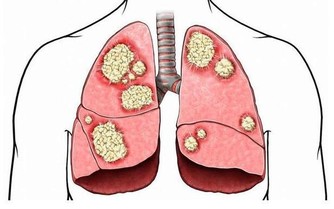

大拇指對應人體肺經,肺主納氣,如果肺不好,那麼心也會受到影響。當出現心慌、胸悶等情況時,可用手刮大拇指外側並往外拉。 另外,肺不好,容易影響脾胃功能,所以脾胃功能差的人,也可以做此動作。 便秘 刮食指